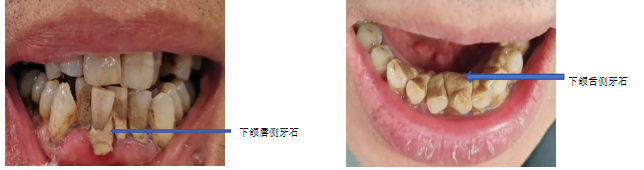

��ʯ�dz�����������������Ѹƻ������ڸƻ��ľ������������Һ������Һ�еĿ������������ɡ���ʯ�γɺ���ͨ���ճ�ˢ�����������ȼ�ͥ�ֶγ���ȥ������������רҵ���Ʋ������ճ���������Ԥ�����ٴ��γɡ���ʯ���ݳ����IJ�λ����������ԵΪ�磬�ɷ�Ϊ������ʯ��������ʯ��

��ʯһ���γɣ������Ρ�ճ�� �����ݱ��档���Ŀ��ᄃ������ݵ������ʡ������ʵȲ�λ����ܽ�ϣ������� ��Ƕ���� һ���������γ�Ȯ�ݽ�������Ƕʽ���ţ���Ҳ������ʯ���ѱ�������������ؼ����ǣ���ʯ�ı���ʼ�ջḲ����һ����ߣ���Ϊ��ǻϸ���� �������ء���

��һ���Ǵ����֪��ϴ����ҽѧ�Ͻ����Ͻ���������ר�Ŵ������ݱ��桢������Ե���ϵ���ʯ��ҽ�����ó�����������ͨ������ʯ������������˳������ȥ�������ϵ�ɫ�غ������ߣ�����ٸ������⣬�������⻬�����ٺ�����ʯ���š�

�ڶ��������¹��μӸ���ƽ������Ե��Dz��������������ʯ��������ʯ���������������ף�ҽ�����þ�ϸ��ר�ù��ߣ��쵽�����������ʯ�ͱ���Ⱦ����������ɾ����ٰ���������ĥƽ��������ϸ��������ռ䣬����������֯�ָ�������